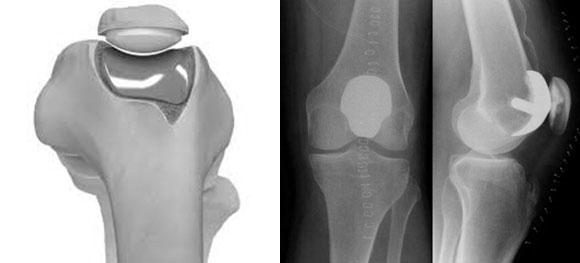

Эндопротезирование пателлофеморального соединения

Под данным методом подразумевается полная замена надколенника и части бедренной кости. Этот способ лечения уместен в тех редких ситуациях, когда повреждения костной ткани затрагивают только поверхность коленной чашечки и соседние области.